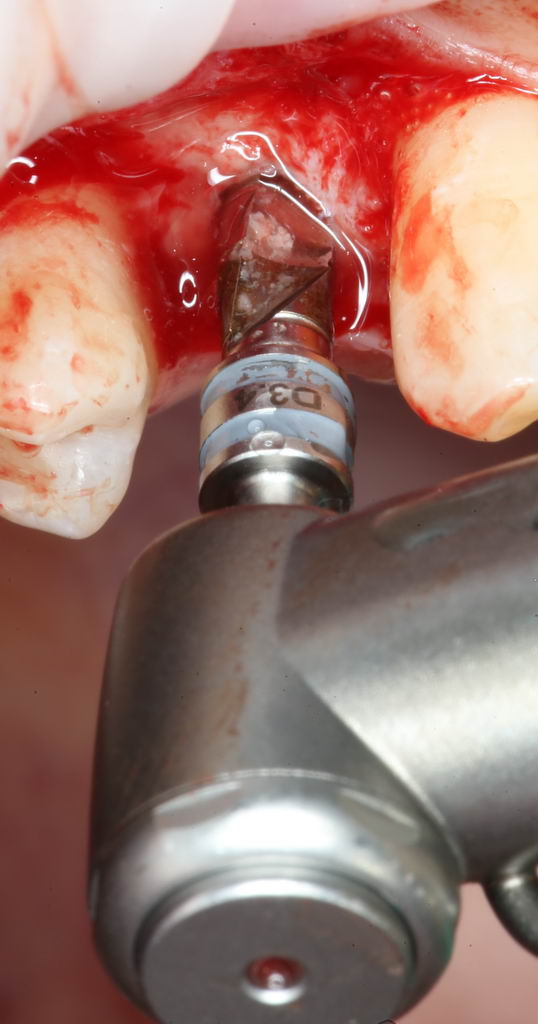

А всё потому, что костная ткань — упругая среда, и чтобы снять напряжение с кортикальной пластинки (и предотвратить периимплантит) мы используем специальную кортикальную фрезу:

И вот теперь, уважаемые друзья, мы можем приступить к установке имплантата.